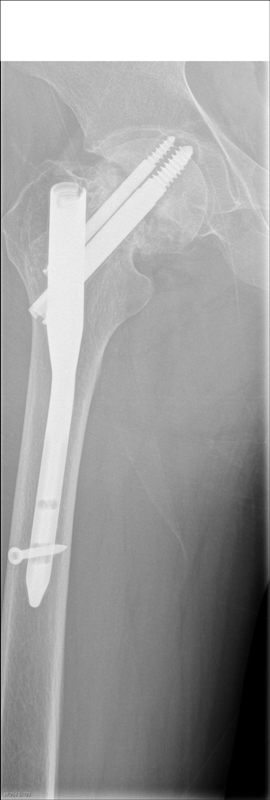

Добрый день уважаемые коллеги! Помогите с определением фирмы производителя данной конструкции.

Из анамнеза: установлен два года назад в г. Грозный. Заранее спасибо.

Похоже на произведение предприятия ЦИТО.

похоже на Bi Nail GRUPPO BIOIMPIANTI

Нет-это не Bi Nail GRUPPO BIOIMPIANTI,мне это больше напоминает польский ChM.Только какая разница шеечные винты не фиксированы,выйдут легко.

Medin Чехия

Strayker - сто в гору даю

У Страйкера никогда не было конструкций с 2-мя винтами...

Похоже, стержень неканюлированный, видел такие в СнМ.